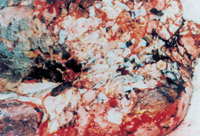

患者入院時,病情嚴(yán)重,處于休克狀態(tài)。大面積深度燒傷創(chuàng)面被水泥粉貼覆,鼻毛燒焦,水泥呼吸道吸入,呼吸音變調(diào),聲音嘶啞,緊急作氣管切開,對創(chuàng)面行MEBT/MEBO加耕耘療法治療,對全身進(jìn)行綜合治療,創(chuàng)面組織學(xué)檢查為Ⅲ度燒傷。

3-17 取燒傷皮膚組織進(jìn)行組織切片,診斷為全厚皮壞死,部分脂肪層組織壞死